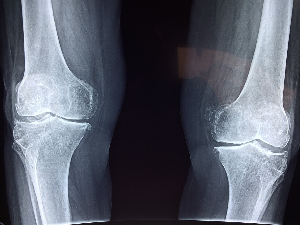

100세 시대, 건강한 관절은 곧 건강하고 활기찬 삶과 직결됩니다.

아픈 곳 없이 건강한 생활을 위해서 손쉽게 할 수 있는 것이 올바른 음식을 섭취하여 관절 건강을 개선, 유지하는 겁니다.

관절에 생기를 불어넣어 줄 관절에 좋은 음식 BEST 5를 알아보고, 건강한 삶을 누리시기 바랍니다.